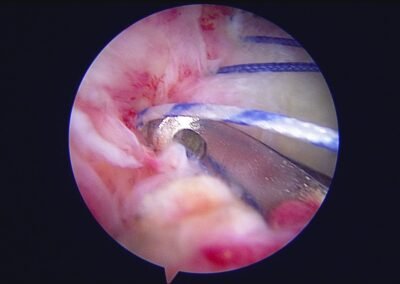

GalleryShoulder rotator cuff repair Meniscus root repair Meniscus repair Bankart repair for recurrent shoulder dislocation ACL reconstruction Machines Instruments